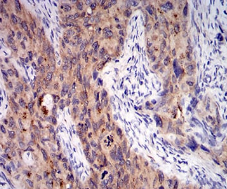

IHC    1/200 - 1/1000